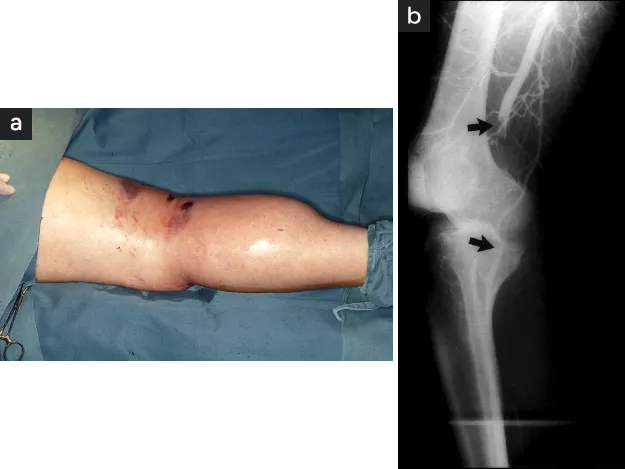

血行障害の再発は感染壊疽を急速に悪化させて、重要骨骨髄炎〈図2〉や化膿性足関節炎〈図3〉など切断必至の合併症を発生する可能性があるため下肢救済が完全に達成されるまでは余談を許さない病状が続きます。